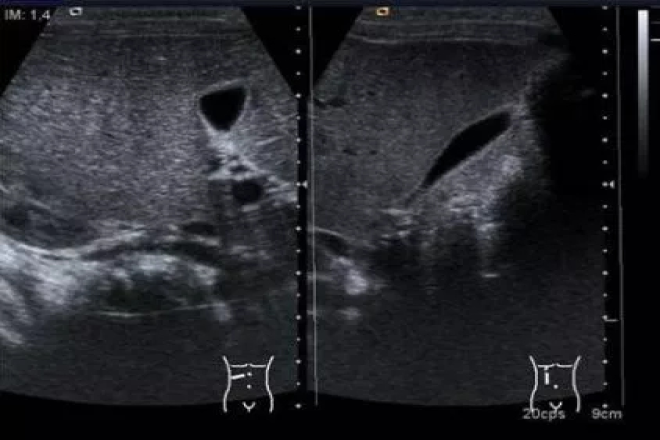

Vesícula biliar